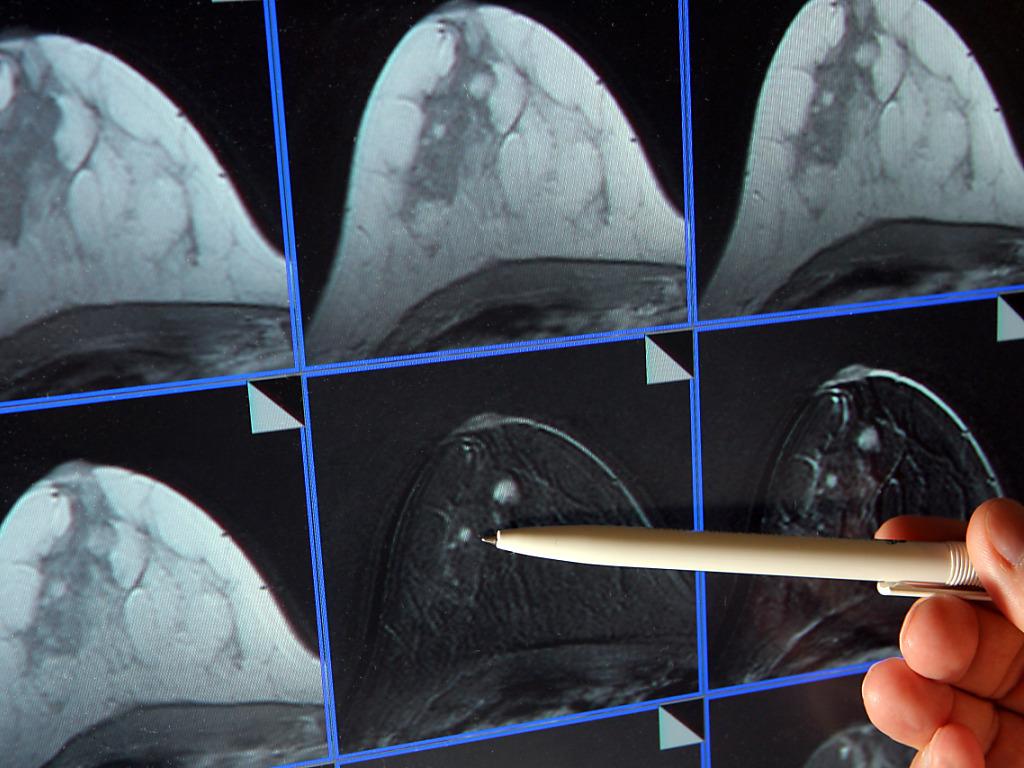

Il cancro alla ghiandola mammaria umana si sviluppa preferibilmente nelle parti esterne, vicino all’ascella, dove la pelle è molto sottile e permeabile. Da anni ricercatori lavorano sull’ipotesi che i sali di alluminio, presenti in alte concentrazioni in deodoranti e certe creme solari, possano essere tra le cause che provocano l’insorgere della malattia.